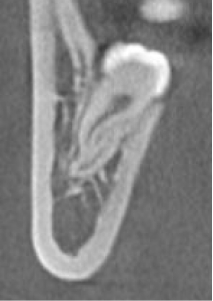

CBCT具有扫描速度快,空间分辨率高,辐射剂量小,图像伪影小等优点,其对颌面、牙齿、骨骼的良好成像效果,高质量的三维立体图像,图像精度提高,无几何失真,可以进行清晰的实际测量。此外,放射剂量更小,尽管高于普通平片,但由于能够满足传统检查无法实现的诊断需求,因此,被广泛用于口腔科临床诊断和治疗,有助于临床做出精确诊断及临床治疗计划的制定与实施。适应症分别有:正畸:三维头影测量、气道分析、正畸种植支抗定位。修复种植:评估患者的骨质、骨量、并掌握下颌神经管、鼻底上颌窦等重要的位置,可以方便设计和制作手术导板。牙体牙髓:疑难根管、遗漏根管及钙化根管的影像诊断。牙周:牙周病的评估。口腔颌面外科:埋伏牙、阻生牙、多生牙的三维定位、颌面部骨折、颞下颌关节紊乱的诊断。

(牙体牙髓医生可以通过CBCT观察需治疗牙的牙根数目及形态)